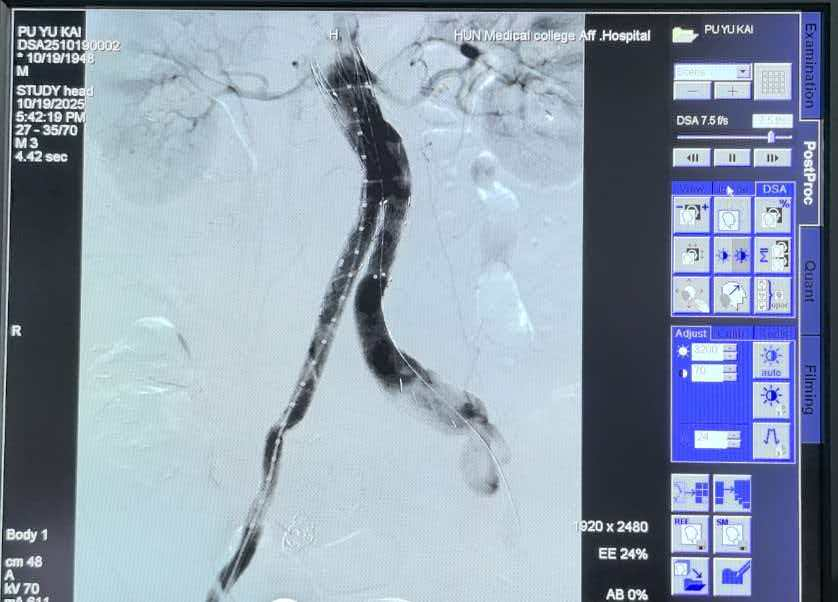

针对下肢深静脉血栓形成(DVT),建立“下腔静脉滤器植入+急性期导管接触性溶栓/血栓抽吸/取栓支架取栓”的规范化方案,快速缓解下肢肿胀疼痛,降低肺栓塞风险及远期血栓后综合征发生率。在静脉曲张治疗中采用激光闭合术联合泡沫硬化剂注射,患者术后当天即可步行回家,且腿部无明显手术痕迹,在保障疗效的同时兼顾美观,为众多血管疾病患者打通生命“交通线”。

左侧髂压综合征合并混合型左下肢深静脉血栓治疗前后对比